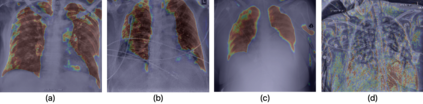

Medical image analysis continues to hold interesting challenges given the subtle characteristics of certain diseases and the significant overlap in appearance between diseases. In this work, we explore the concept of self-attention for tackling such subtleties in and between diseases. To this end, we introduce MEDUSA, a multi-scale encoder-decoder self-attention mechanism tailored for medical image analysis. While self-attention deep convolutional neural network architectures in existing literature center around the notion of multiple isolated lightweight attention mechanisms with limited individual capacities being incorporated at different points in the network architecture, MEDUSA takes a significant departure from this notion by possessing a single, unified self-attention mechanism with significantly higher capacity with multiple attention heads feeding into different scales in the network architecture. To the best of the authors' knowledge, this is the first "single body, multi-scale heads" realization of self-attention and enables explicit global context amongst selective attention at different levels of representational abstractions while still enabling differing local attention context at individual levels of abstractions. With MEDUSA, we obtain state-of-the-art performance on multiple challenging medical image analysis benchmarks including COVIDx, RSNA RICORD, and RSNA Pneumonia Challenge when compared to previous work. Our MEDUSA model is publicly available.